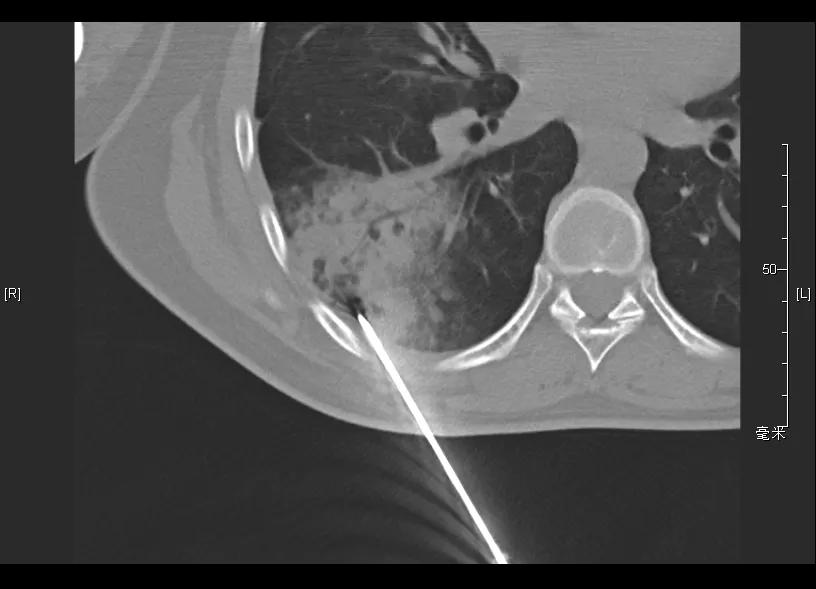

CT引导下肺穿刺活检(2019-05-14)

病理: (肺穿刺)少量支气管壁及肺组织,肺泡间隔明显增宽,可见浆细胞及淋巴细胞浸润,考虑炎症性病变。补充报告:(肺穿刺)特染未提示有血管炎病变。免疫组化:CD31(+),CD34(+)。特殊染色:弹力(-),Masson(-)。

调整治疗方案: 考虑患者机化性肺炎复发,予醋酸泼尼松片15mg qd、硫唑嘌呤片50mg qd治疗,同时辅以兰索拉唑护胃、钙尔奇补钙治疗。